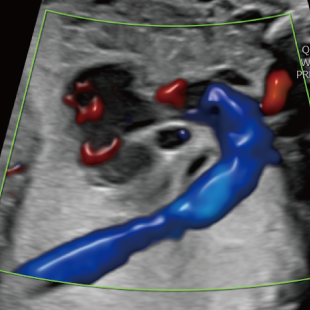

赤ちゃんの3~5%は、何らかの病気や医学的な介入を要する状態をもって生まれてくるといわれており、その中には、妊娠中・出生時・出生後に緊急の対応を要するものも含まれます。 特に先天性心疾患は比較的頻度が高く、約100人に1人の赤ちゃんが先天性心疾患を合併し、重症度や緊急性の高い症例(生後に入院や手術が必要な症例)は約1000人に4人といわれています。

胎児超音波スクリーニングは、このような異常をできるだけ早期に見つけ、赤ちゃんの状態にあわせて安心・安全なご出産を迎えていただくための検査です。もし何らかの異常が見つかった場合にはご出産前に超音波専門医・指導医による精査、必要に応じて臨床遺伝専門医***による遺伝カウンセリング、小児科医・小児外科医による詳細な診察や出生後についてのカウンセリングを受けて頂くことが出来ます。

Voluson Expert 22®(GEHealthcare)という産婦人科領域におけるハイエンド超音波診断装置を使用しています。 従来機種と比べ、より高精細な画像描出性能と高度な解析機能を備えており、 胎児の発育や形態をより詳細に観察することが可能です。